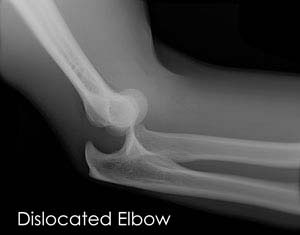

Elbow Dislocation

The elbow is a hinge joint made up of 3 bones – humerus, radius and ulna. The bones are held together by ligaments to provide stability to the joint. Muscles and tendons move the bones around each other and help in performing various activities. Elbow dislocation occurs when the bones that make up the joint are forced out of alignment.